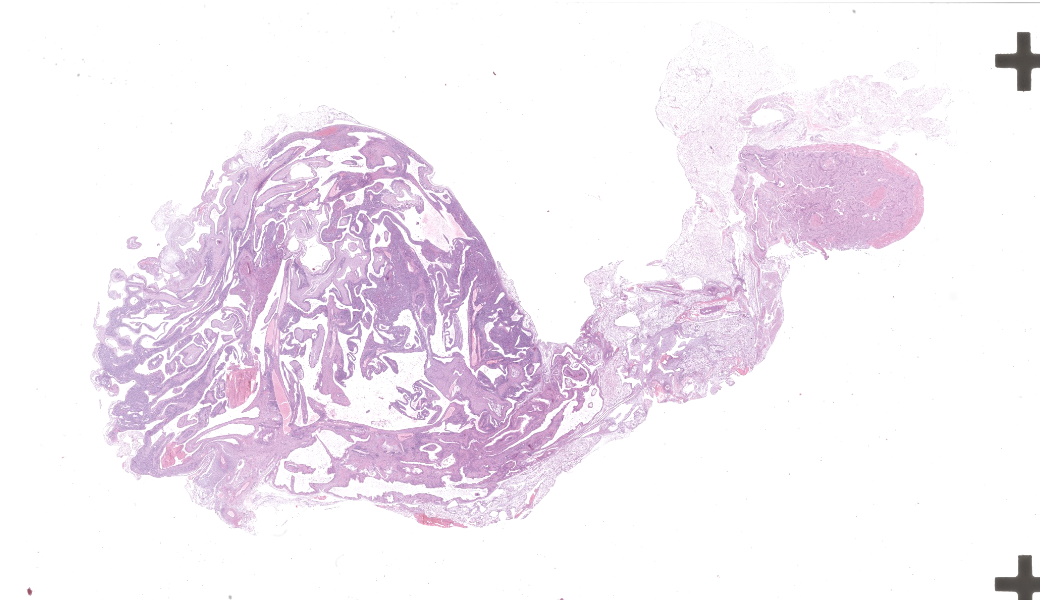

Microscopic Description:

Left kidney: The left kidney is composed of multiple, largely dilated cavities that divide the kidney into numerous islands of parenchyma. These cavities are lined by 2–4 layers of cuboidal to highly columnar, eosinophilic epithelial cells with no mitotic activity (collecting ducts). Few sloughed epithelial cells and erythrocytes are present in the lumen of these ducts. The parenchyma contains islands of immature glomeruli with peripheral nuclei, poorly developed capillaries, and thickened Bowman’s capsule (vimentin positive). Primitive tubules are lined by large basophilic cuboidal epithelial cells with minimal or absent lumina. Other areas within the parenchyma consist of mature tubules and glomeruli with some tubules showing mild dilation and intraluminal protein casts. Collecting duct-like structures are multifocally surrounded by loosely arranged mesenchymal tissue (primitive mesenchyme). The interstitium is multifocally expanded by fibrous connective tissue and some areas are infiltrated by low to intermediate numbers of lymphocytes, plasma cells, macrophages, and occasional neutrophils. Some arteries are very prominent (large) with thickened media, and they appear tortuous. A medium sized artery is surrounded and infiltrated by inflammatory cells predominantely macrophages, neutrophils and occasionally multinucleated giant cells within adventitia, media and intima (transmural). Diffuse proliferation of fibroblasts and deposition of fibrin within the vessel wall is observed. Occasionally, the tunica intima is disrupted. Endothelial cell proliferation is evident with clustering of endothelial cells attempting to recanalize the affected lumina.

Left ureter: Multiple longitudinal and cross-sections of the ureter are present, consisting of urothelium, lamina propria, a smooth muscle layer, and an outer adventitial layer. The periureteral mesenchymal tissue similar to persistent mesenchyme was observed surrounding left ureter and multifocally contains fibrin and exhibits multifocal moderate hemorrhage, and is infiltrated by inflammatory cells, predominantly neutrophils and macrophages, with the presence of hemosiderophages.

- Multicystic renal dysplasia with focal rupture of the capsule.

- Mild to moderate multifocal chronic lymphoplasmacytic tubulointerstitial nephritis.

- Severe diffuse chronic histiocytic arteritis

- Kidney: Congenital hydronephrosis, severe, with tubular and glomerular atrophy, interstitial fibrosis, mild lymphoplasmacytic interstitial nephritis.

- Kidney: Asynchronous maturation, with fetal glomeruli, rare primitive tubules, and primitive mesenchyme.

- Kidney, arteries and arterioles: Arteritis, neutrophilic and histiocytic, proliferative and necrotizing, chronic, multifocal, severe.